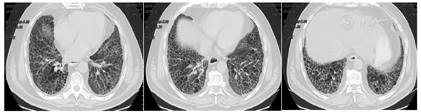

患者,男性,61岁,因"活动后憋气伴咳嗽半年余,胸痛5 d"入院。患者半年前(2019年11月)受凉后出现胸闷、憋气,活动后为著,伴咳嗽,无痰,休息后症状可缓解,就诊于我院,行胸部CT示肺间质纤维化,右肺下叶团片影(图1),予以抗感染、止咳、平喘等治疗。患者拒绝进一步检查明确右肺下叶团片影性质,后症状好转,准予出院。5天前(2020年4月16日)受凉后出现胸痛,深呼吸时加重,仍有活动后胸闷憋气,伴咳嗽,夜间可平卧入睡。患者自发病以来,饮食、睡眠尚可,大小便正常,近期体重无明显改变。患者既往有肺间质纤维化、干燥综合征、高血压等病史,无吸烟史。

2020年4月21日胸部CT平扫(图2):1.双肺间质纤维化合并感染,建议治疗后复查;2.右肺下叶团片影,较前2020年1月27日CT片范围增大,肺癌不能除外,建议穿刺活检;3.右肺门及纵隔肿大淋巴结较前增大;4.主动脉壁硬化;5.双侧胸膜肥厚;6.脂肪肝。2020年4月27日浅表包块彩色多普勒超声:双侧锁骨上区淋巴结肿大,建议必要时超声引导下穿刺活检。于2020年4月27日在超声引导下右侧锁骨上淋巴结穿刺活检术。2020年4月28日病理回报:(右颈部淋巴结)灰白穿刺组织3条,长均0.8 cm,直径均0.1 cm。病理诊断:(右颈部淋巴结穿刺组织)穿刺组织中见淋巴组织、坏死及异型细胞团,诊断为鳞状细胞癌转移。基因检测:EGFR(-),PD-L1 TPS 78%。